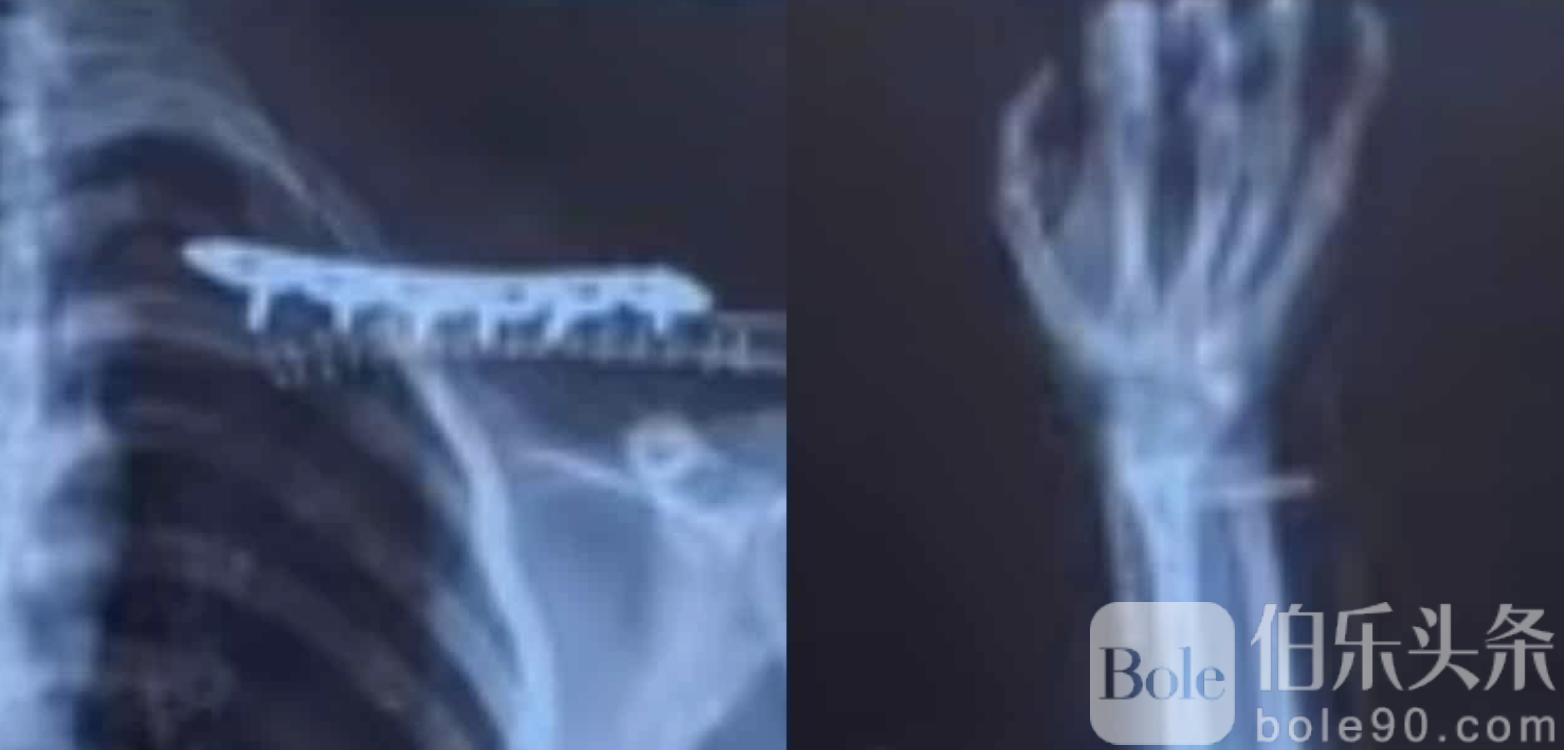

事故造成男性摩托车骑士当场死亡,拉敏·凯因则伤势严重,手腕骨折、锁骨断裂,被紧急送医治疗。医生评估,其伤势完全恢复可能需要两年以上时间,期间将严重影响其日常生活及学业,尤其是无法正常参与实验课程和体育活动。